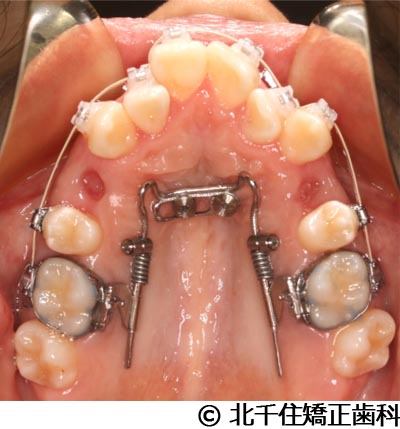

【症例2】上顎前突症

- 治療中

主訴:出っ歯、口元の突出、横顔をきれいにしたい

治療方法

骨格性の上顎前突、上下顎第一小臼歯4本及び上顎第二大臼歯を抜歯して矯正用アンカースクリューを併用してワイヤー矯正治療(セラミックブラケット)。

治療結果

骨格性上顎前突に対し、抜歯および矯正用アンカースクリューを併用した矯正治療により歯列および咬合関係の調整を行った症例である。治療後は保定装置を使用し、歯列および咬合の安定維持を目的として定期的な経過観察を行っている。

※治療結果は個人差があります。

治療を行う上での注意点(リスク・副作用)

歯磨き不良に伴うカリエスや歯周病、顎関節症、歯根吸収など。